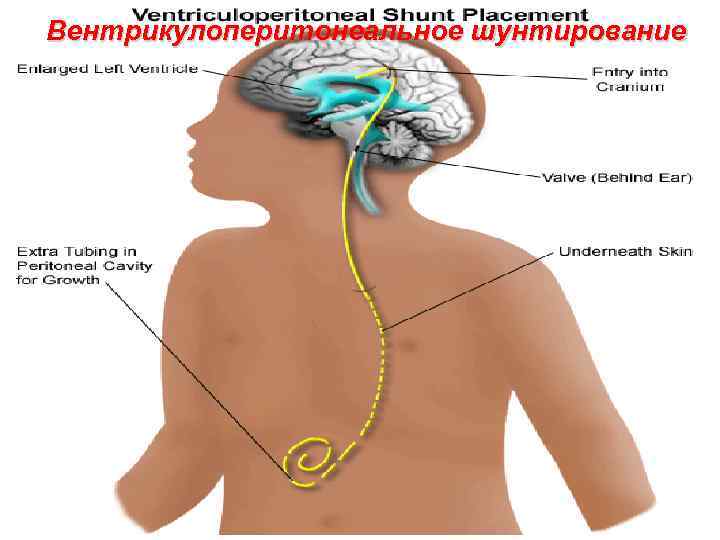

Вентрикулоперитонеальное шунтирование 99